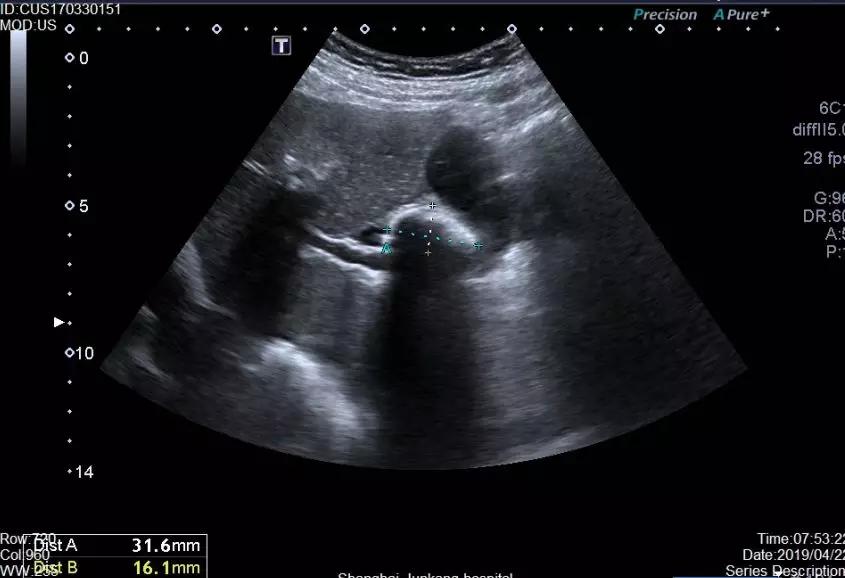

胆结石又称胆石症,是发生在胆囊和胆管的结石总称,通常是由于肝脏代谢障碍或者胆道运动功能失调,引起胆汁中的固体成分沉积在胆囊和胆管中形成的。发生胆结石,轻者可无任何临床表现,或仅仅有轻微消化不良症状,重者会引发会引发胆绞痛,胆囊化脓、穿孔、黄疸、胰腺炎,严重的甚至会发生癌变。